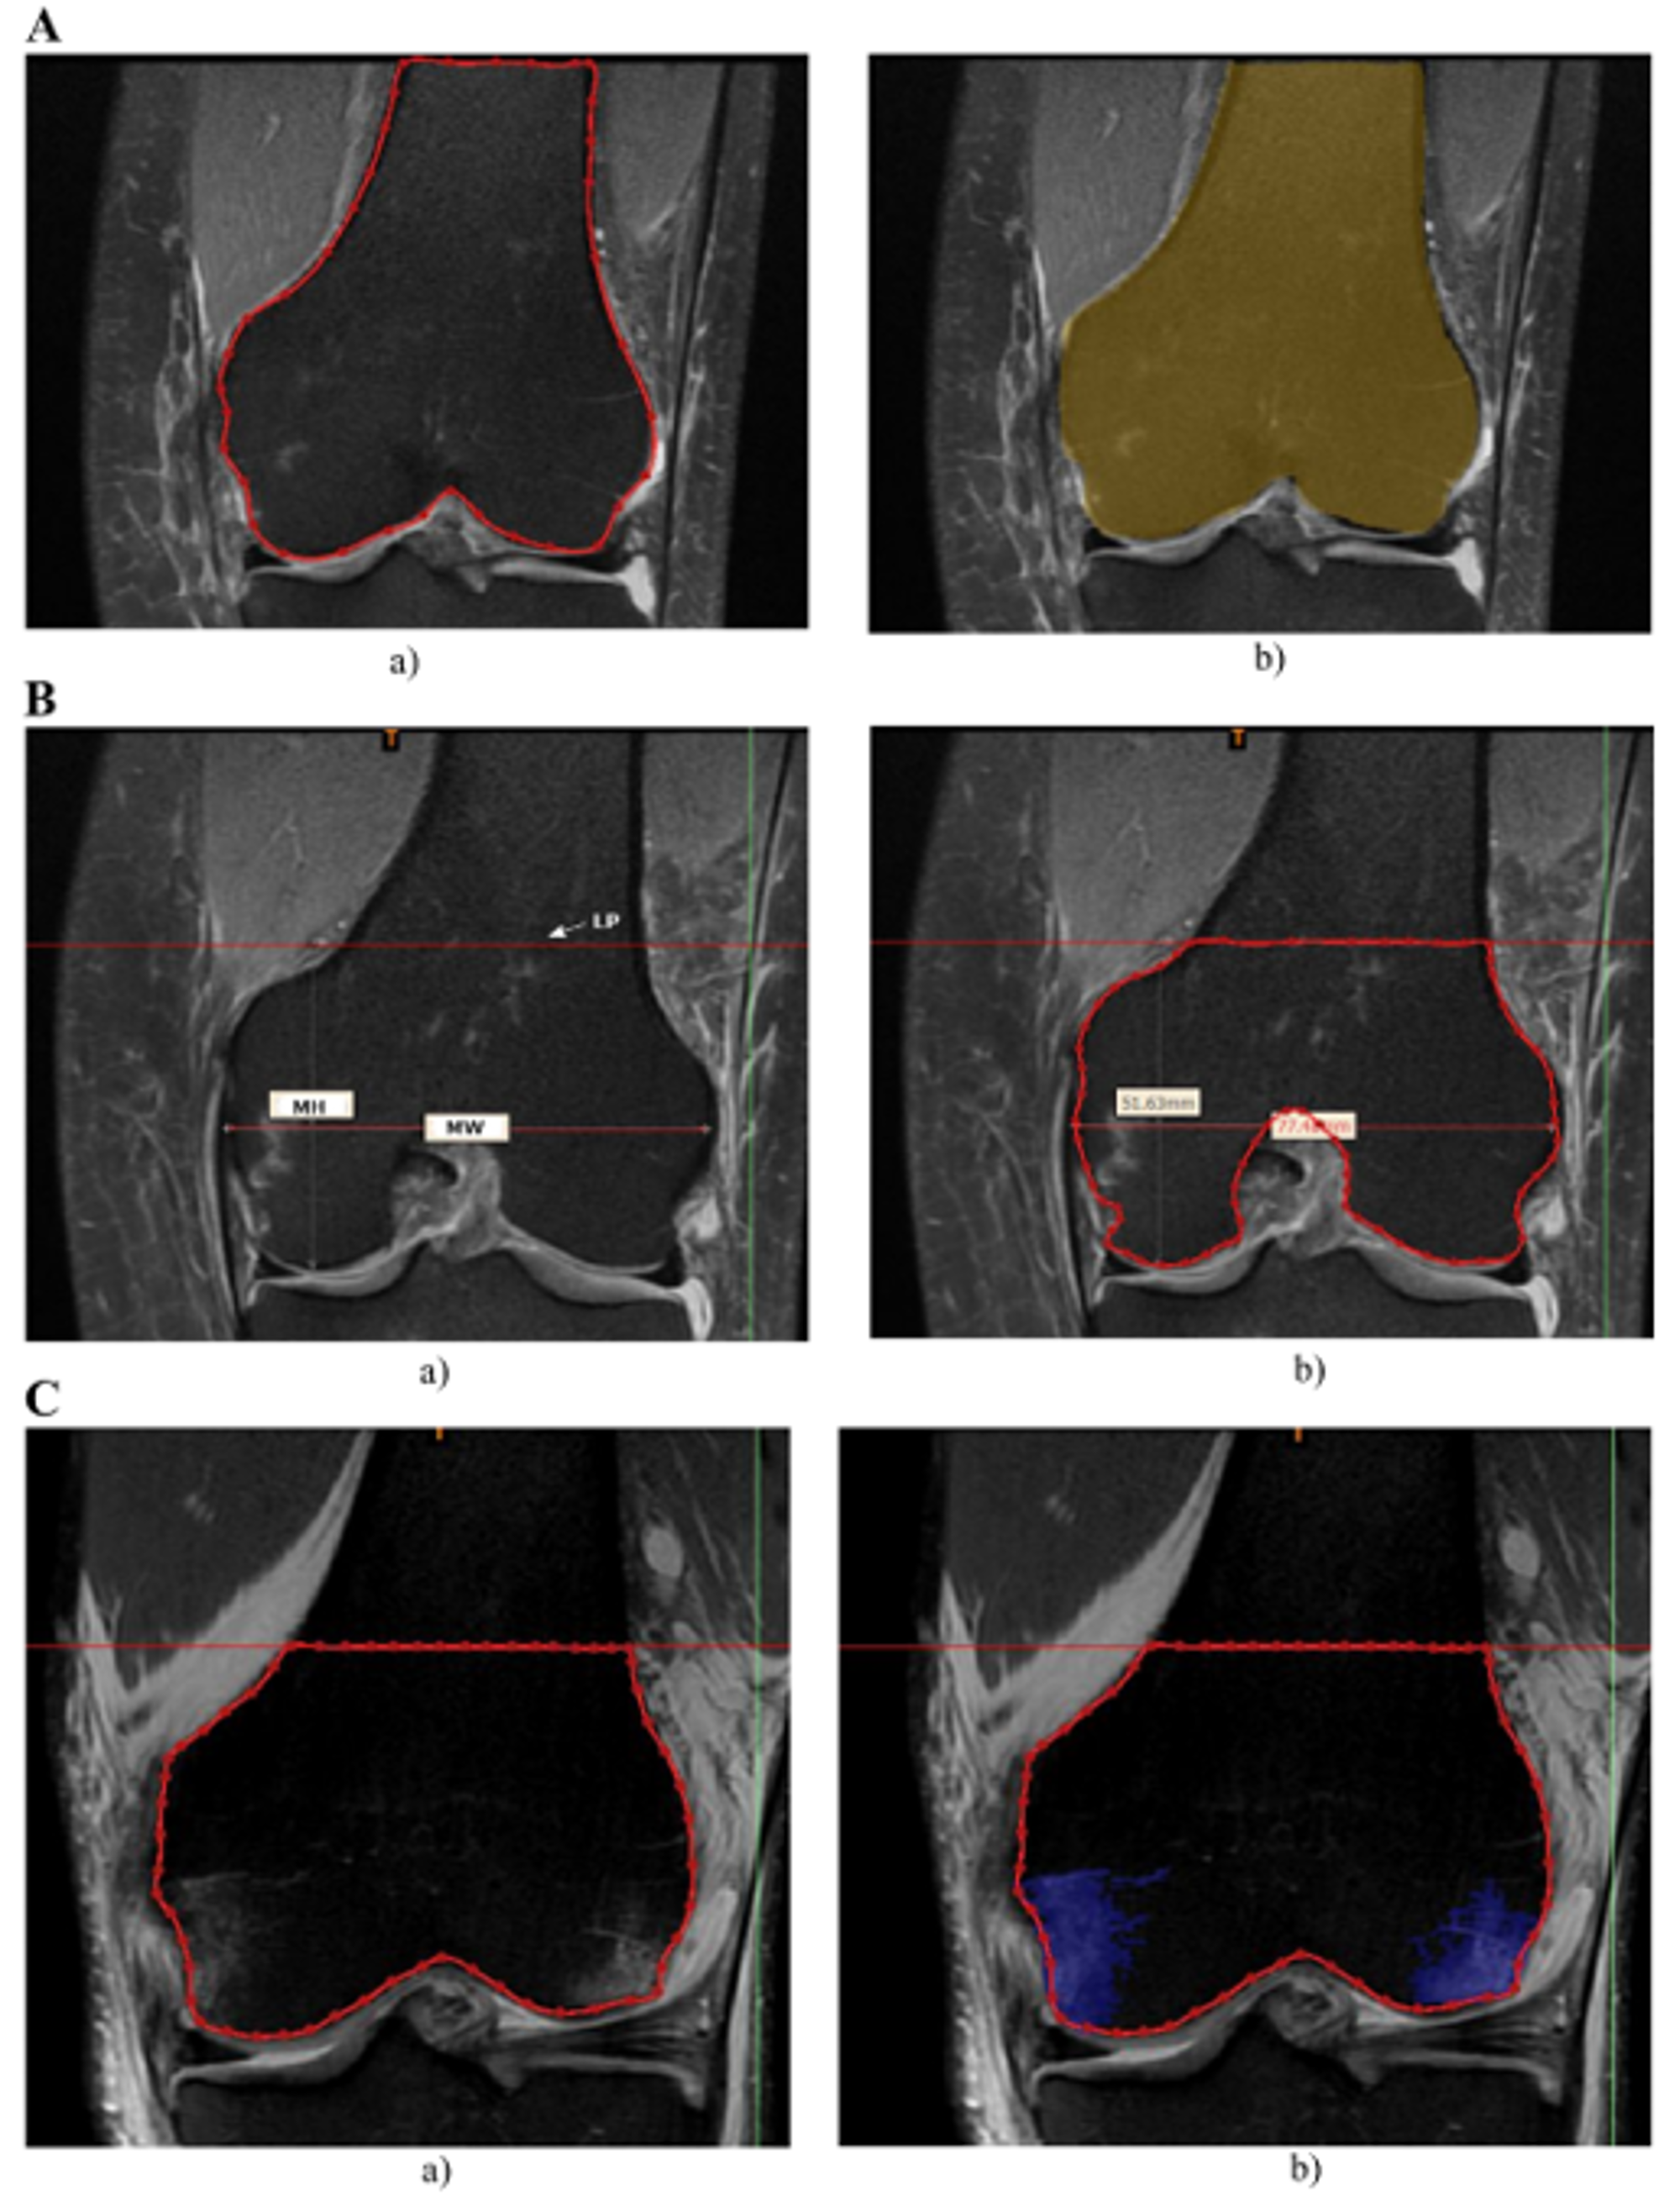

2.3. Segmentation of BB

- in femur:

- in tibia:

2.5. Spatial Characteristics of Bone Bruises in Correlation to Bone Tunnel Location